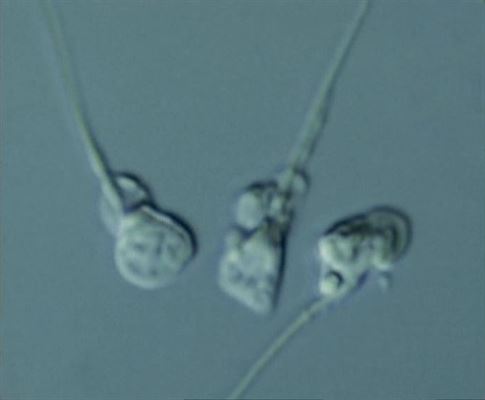

IMSI işleminde görülen sperm

8050 büyütme

Baş anomalileri kolaylıkla seçilebilmekte

(solda normal, sağda anormal baş)